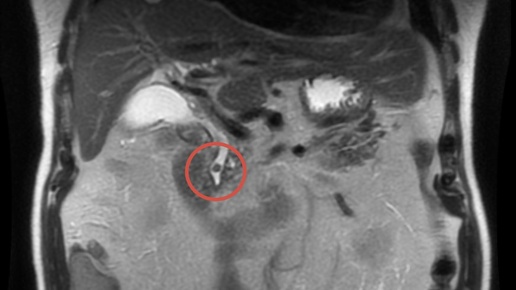

Мужчина 77 лет. Выраженная резкая боль в эпигастрии до 10/10 по визуально-аналоговой шкале, иррадиация в спину, выраженная тошнота.

- Боль в верхней части живота в течение нескольких дней - Самостоятельный приём препаратов «от желудка» — кратковременный эффект - Утром — резкое усиление боли - Спазмолитики и НПВС без эффекта - Гемодинамика относительно стабильна - Живот вздут, болезненность в эпигастрии - SpO₂ 92% - Перитонеальных симптомов нет - Общий билирубин 85 мкмоль/л, прямой 32 мкмоль/л - Умеренное повышение АСТ/АЛТ - CRP 38 мг/л - Лейкоцитоз с нейтрофилёзом - Hb 193 г/л, Ht до 60% - Липаза и амилаза — в норме ➡️ патологии...